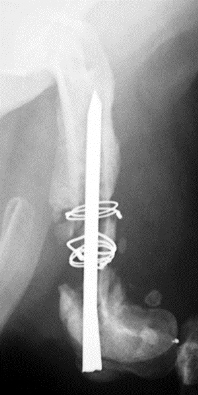

獣医外科学研究室では、およそ9年前から再生医療に関する研究を行っています。骨髄や脂肪組織中に存在する幹細胞に関する研究や、各種サイトカインの研究などから実際の臨床応用に必要な数多くの成果を得てきました。現在では本学付属動物医療センターにて主に骨再生および脊髄再生に関する臨床試験を実施し、その有用性および安全性を調査しています。

図2大腿骨骨幹部に大きな骨欠損を伴う骨癒合不全症例

図3BMP(骨形成タンパク)を使用した骨再生治療(治療中)

図4骨再生治療終了時の状態(周囲の骨と一体化した骨組織が再生している)